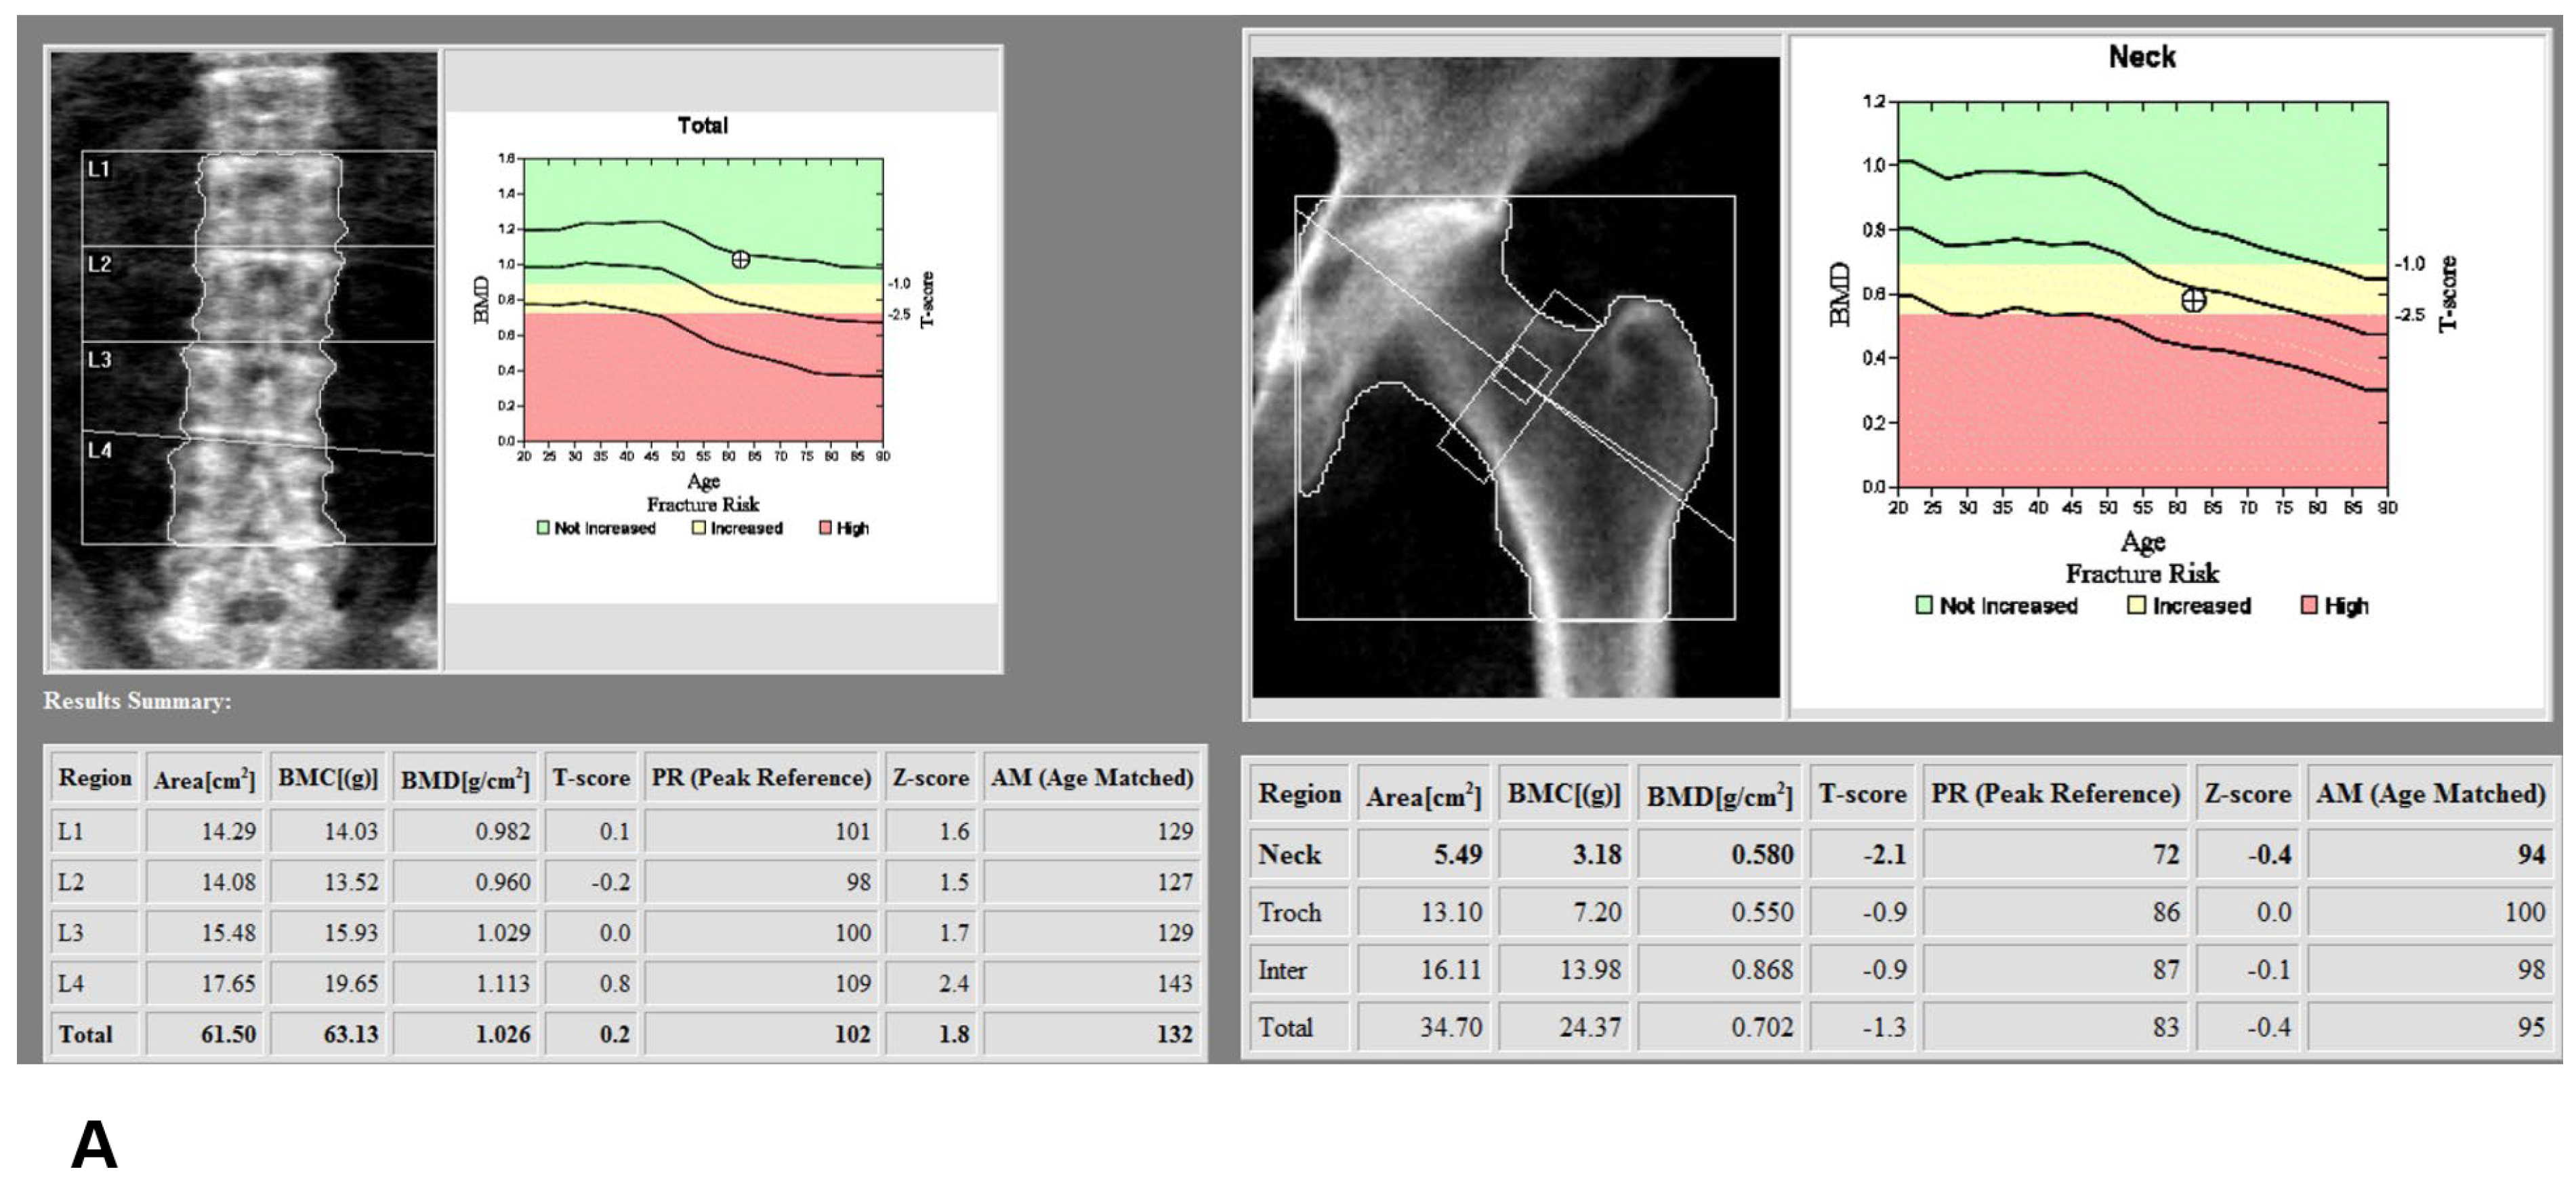

Figure 2.

(A) Assessment of dual x-ray absorptiometry (DXA) in the lumbar spine and femur neck; (B) Manual definition of the region of interest (ROI) and assessment of bone mineral density (BMD) derived from dual-energy computed tomography (DECT) in the distal femur and proximal tibia using dedicated DECT postprocessing software; (C) Manual definition of the region of interest (ROI) and assessment of Hounsfield unit (HU) derived from dual-energy computed tomography (DECT) in the distal femur and proximal tibia using dedicated DECT postprocessing software.

Phantomless volumetric BMD assessment of L2 and the left femur neck with DECT requires manual delineation of trabecular volumes of interest (VOI) in the L2 vertebra and the left pelvis, which was carried out by one of the authors with dedicated software (Examine, Siemens Healthcare, Erlangen, Germany). Regions of interest (ROIs) defined to best include trabecular bone and exclude any cortical bone were also drawn manually on the images loaded into the software (Figure 2B). The software then performed calculations according to a dedicated algorithm and the resulting output included the volumetric BMD values.

For DECT HU analysis, one of the authors, working at a conventional PACS workstation, manually defined polygonal ROIs on standard bone reconstructions in sagittal or axial image series (Figure 2C). The ROIs were positioned in the anterior trabecular bone space of the L2 vertebral body, as proposed by several studies [,,]. Thereby, the reader was instructed to avoid attenuation heterogeneity by placing the ROIs in areas of spinal hemangiomas or other causes of attenuation heterogeneity. All HU values were obtained as averages of three serial polygonal ROIs.